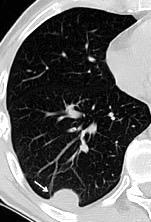

66 pacientes con

Tb pleural probada

Ocasionalmente nivel hidro-aéreo por fístula broncopleural Consolidación........3% Ganglios……….....39%

Derrame...................65-98.5%

Lesiones pleurales. ........38 %

Afect. cisura interlobar….9%

Pl. mediastínica........... 1.5%

Afect. pulmonar 26/66 … 39%

Cambios fibróticos..........17%

Cavitación ......................12%

Nódulos heterogéneos.....6%